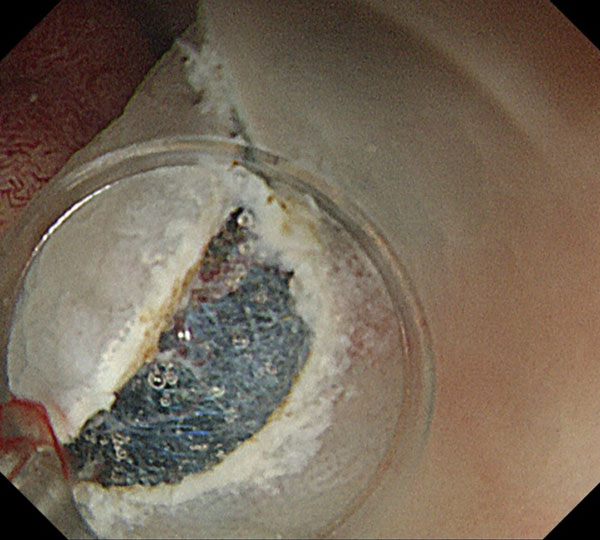

ESDの手法としては、浸水下ポケットクリエーション法を主体に行っています。脱気した状態で行うため、患者さんも楽に受けられ、筋層直上で安定して切除できるため、繊維化がある病変の切除も容易です。切除された標本の状態も良好で、正確な病理学的評価が可能です。

5. 内視鏡先端が挿入できるほど剥離が進むと、内視鏡が安定し、粘膜下層を直視しながら筋層直上のラインで正確な剥離操作が可能となります。粘膜下層に軽度の線維化を認めますが、この程度の線維化は剥離には全く問題ありません。周囲粘膜を切開していないため剥離が終了するまで粘膜下層の良好な膨隆が得られます。

7. 十分に剥離したのち、残った粘膜を切開し切除が終了しました。